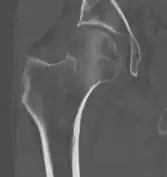

4) Данные рентгенологического обследования — выполняется рентгенография тазобедренного сустава в прямой проекции. Наличие линии перелома на рентгенограмме служит окончательным, объективным подтверждением предварительно выставленного диагноза. Иногда для постановки диагноза может потребоваться магнитно-резонансная томография или компьютерная томография.

В большинстве случаев достаточно выполнения рентгенограммы в прямой проекции. В ситуациях, когда есть подозрение на перелом шейки бедра, но оно не выявлено на рентгеновском снимке, следующим методом исследования является КТ. В редких случаях для подтверждения диагноза используется МРТ — диагностика.

Случай, демонстрирующий возможный порядок исследования изначально незаметных проявлений:

Заключение о виде перелома делается обычно на основании рентгенограмм во фронтальной проекции или КТ-картины. Правильное определение типа перелома позволяет выбрать тактику лечения, которая может существенно различаться для того или иного вида повреждения.